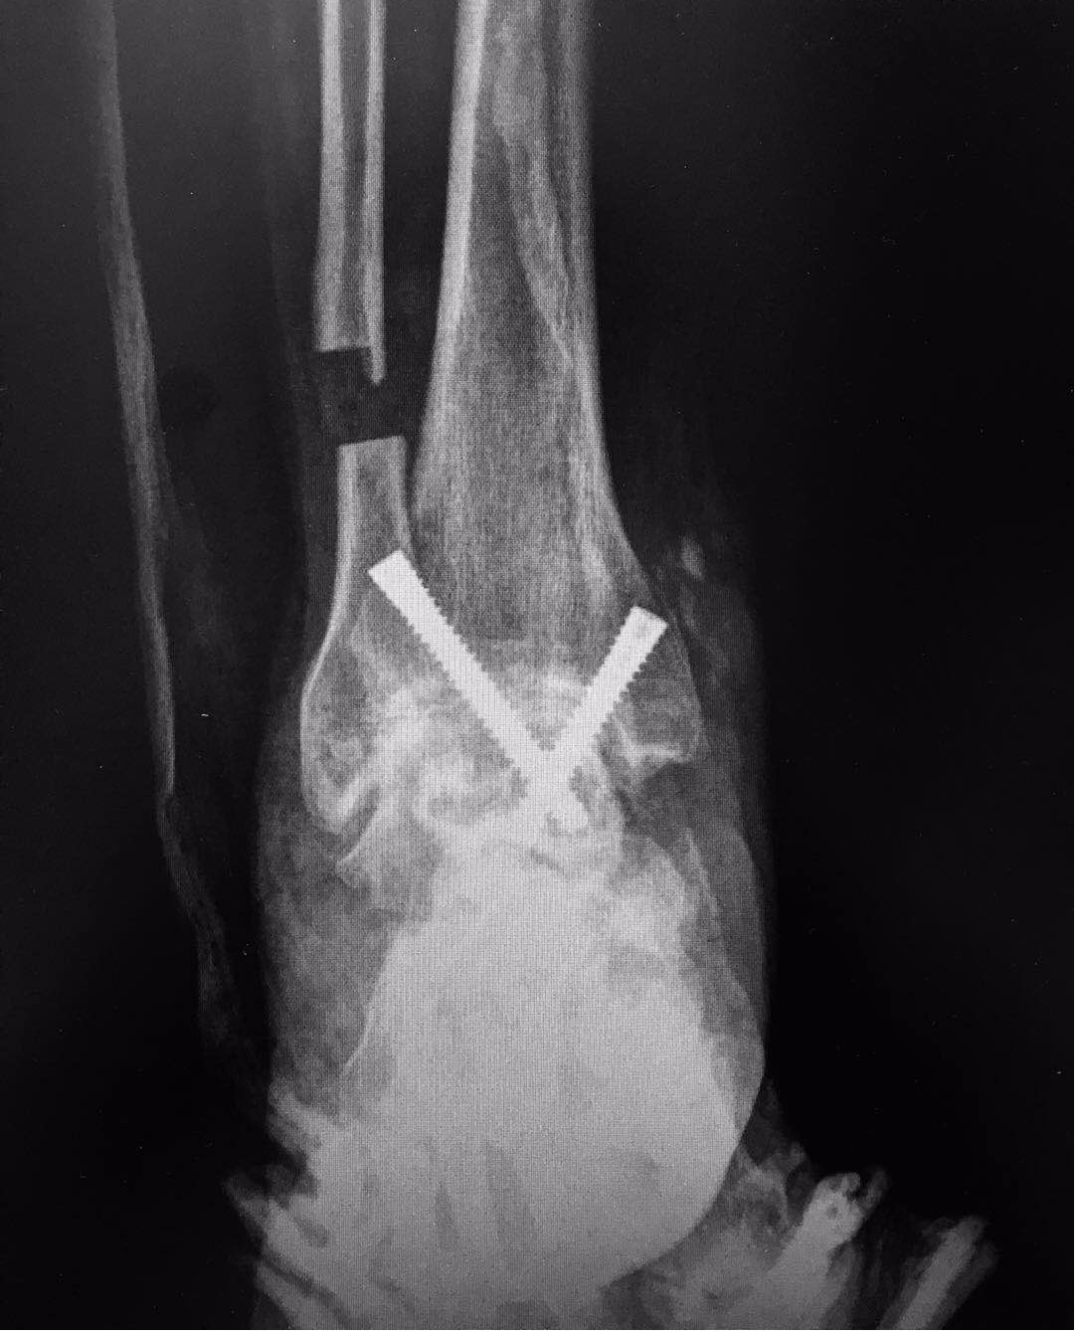

術(shù)后,患者復(fù)查X線顯示:內(nèi)固定位置良好。現(xiàn)已開始逐步進行術(shù)后功能鍛煉,預(yù)計兩周后便可下地行走。